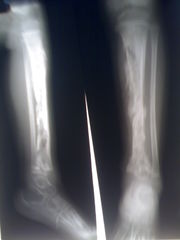

Osteomyelitida

Osteomyelitida (osteomyelitis), česky zánět kostní dřeně, je infekční hnisavé onemocnění kostí a kostní dřeně vyvolané bakteriemi či mykobakteriemi. Při tomto onemocnění dochází k ucpávání cév v kosti krevními sraženinami a následnému odumírání kostní tkáně. Může docházet k obrůstání postižených částí okosticí.

Při exogenním zánětu se infekce do kosti může šířit z okolní hnisající měkké tkáně nebo přímo při otevřených zlomeninách (posttraumatický zánět) či po operacích zavřených zlomenin nebo neúrazových chorob kostí a kloubů (pooperační zánět).